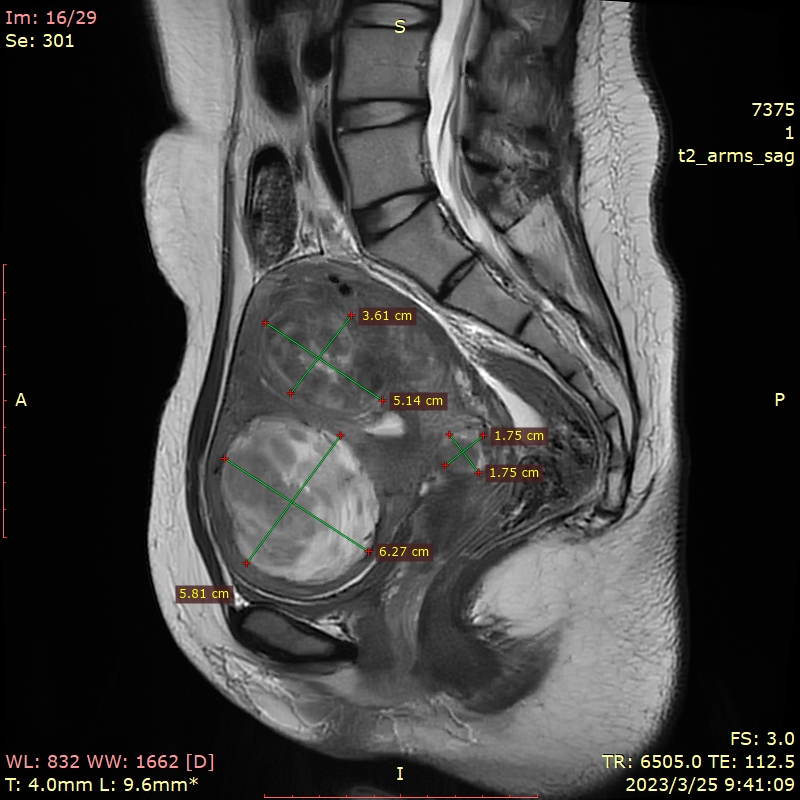

✦超声和MRI提示子宫多发肌瘤,较大者4-5型,T2高信号,71mm*58mm*67mm,次之2型,大小51mm*36mm*55mm,体检提示子宫如孕10周大小。

✦术前肌瘤大小:前壁4-5型肌瘤59mm*52mm,2型肌瘤43mm*40mm。